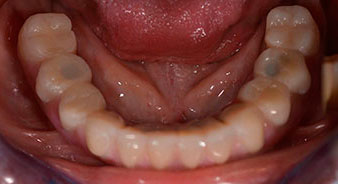

Пациентката е 64-годишна жена с частично обеззъбяване на зъби 38, 33 и 43 и частична долночелюстна протеза (Фиг. 1 и 2).

След изчакване на необходимото време за осеоинтеграция, финалният отпечатък на имплантите е свален и следователно е изработена финалната протеза (Фиг. 19 и 20). В този момент, лекарят по дентална медицина и пациентът могат да обсъдят дали да използват керамични или пластмасови фасети и циркониева или метална рамка. В този случай, екипът на д-р Паску избира пластмасови фасети, имайки предвид неясната прогноза относно частичното обеззъбяване в челюстта и фактът, че зъб 24 е прорастнал. Този вид протеза обикновено е по-лесна за адаптиране и впоследствие може да бъде променяна спрямо новата ситуация в челюстта.